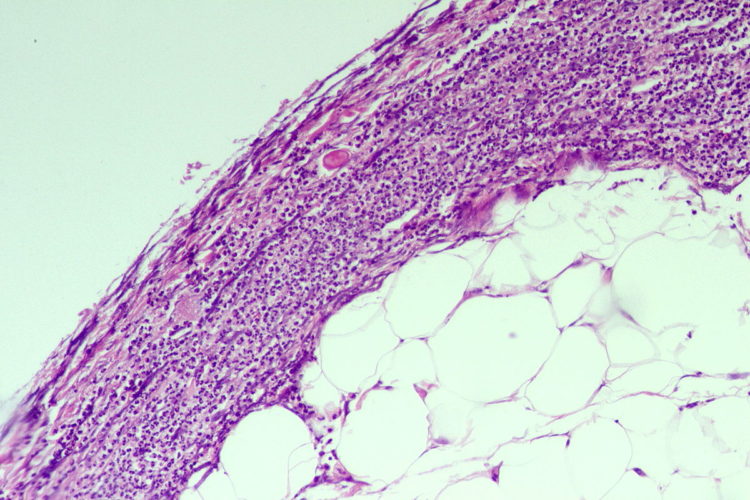

Pathology Outlines COVID19 associated colitis

Pathology Outlines Ischemic colitis Ischemic Colitis Covid To our knowledge, there have not been any. — intestinal ischaemia presenting in patients with covid‐19 has to be considered when symptoms of severe. ischemic colitis has been reported to be associated with a hypercoagulable state. Ischemic Colitis Covid.